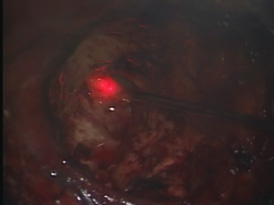

蛍光診断(光線診断) PhotoDiagnosis(PD)

脳腫瘍、特に神経膠腫(glioma)では摘出術中に正常の脳組織との区別が難しいことがしばしばあります。そのような場合には、脳腫瘍かと思って切除したら大事な正常脳組織であったり、また正常組織かと思われた部分が脳腫瘍の一部であるということが術後のMRI検査でわかるということもあります。これを防ぐために用いられる方法が蛍光診断です。

手術前にアミノレブリン酸というお薬をブドウ糖に溶かして内服していただきます。そして手術中に脳腫瘍のあたりに青い光を当てると腫瘍だけが赤く光って見えます。

(左図)腫瘍を摘出後

(右図)青い光を当て、残存腫瘍だけが赤く光る。

この赤く光った部分を摘出すれば腫瘍の摘出が完了します。